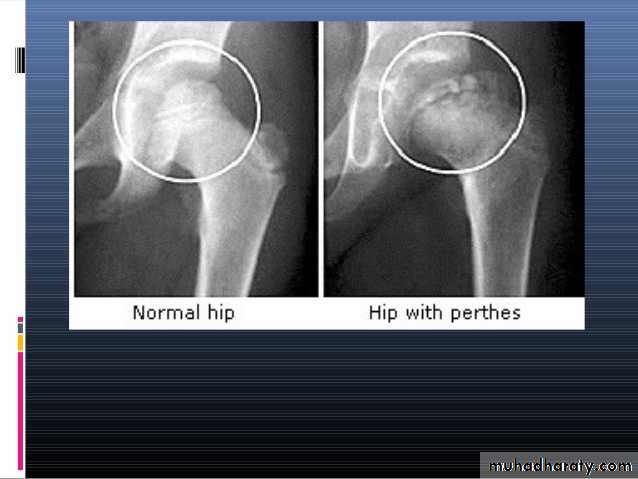

PERTHES’ DISEASE

It is also called Legg – Calve’- Perthes’ disease .

It is painful disorder of childhood characterized by avascular necrosis of the femoral head .

X-ray

1- at the beginning the x- ray look normal some time we can see asymmetry of the ossific centers ; bone scan is helpful at this stage (showing the avascular area) .

2- later on the increase density of the ossific nucleus will be clear ; and there is increase in the joint space .

3- fragmentation of the epiphysis .

4- flattening and lateral displacement of the epiphysis .5- widening of the metaphysis .

6- in sever and advance cases the head become mushroom shape .